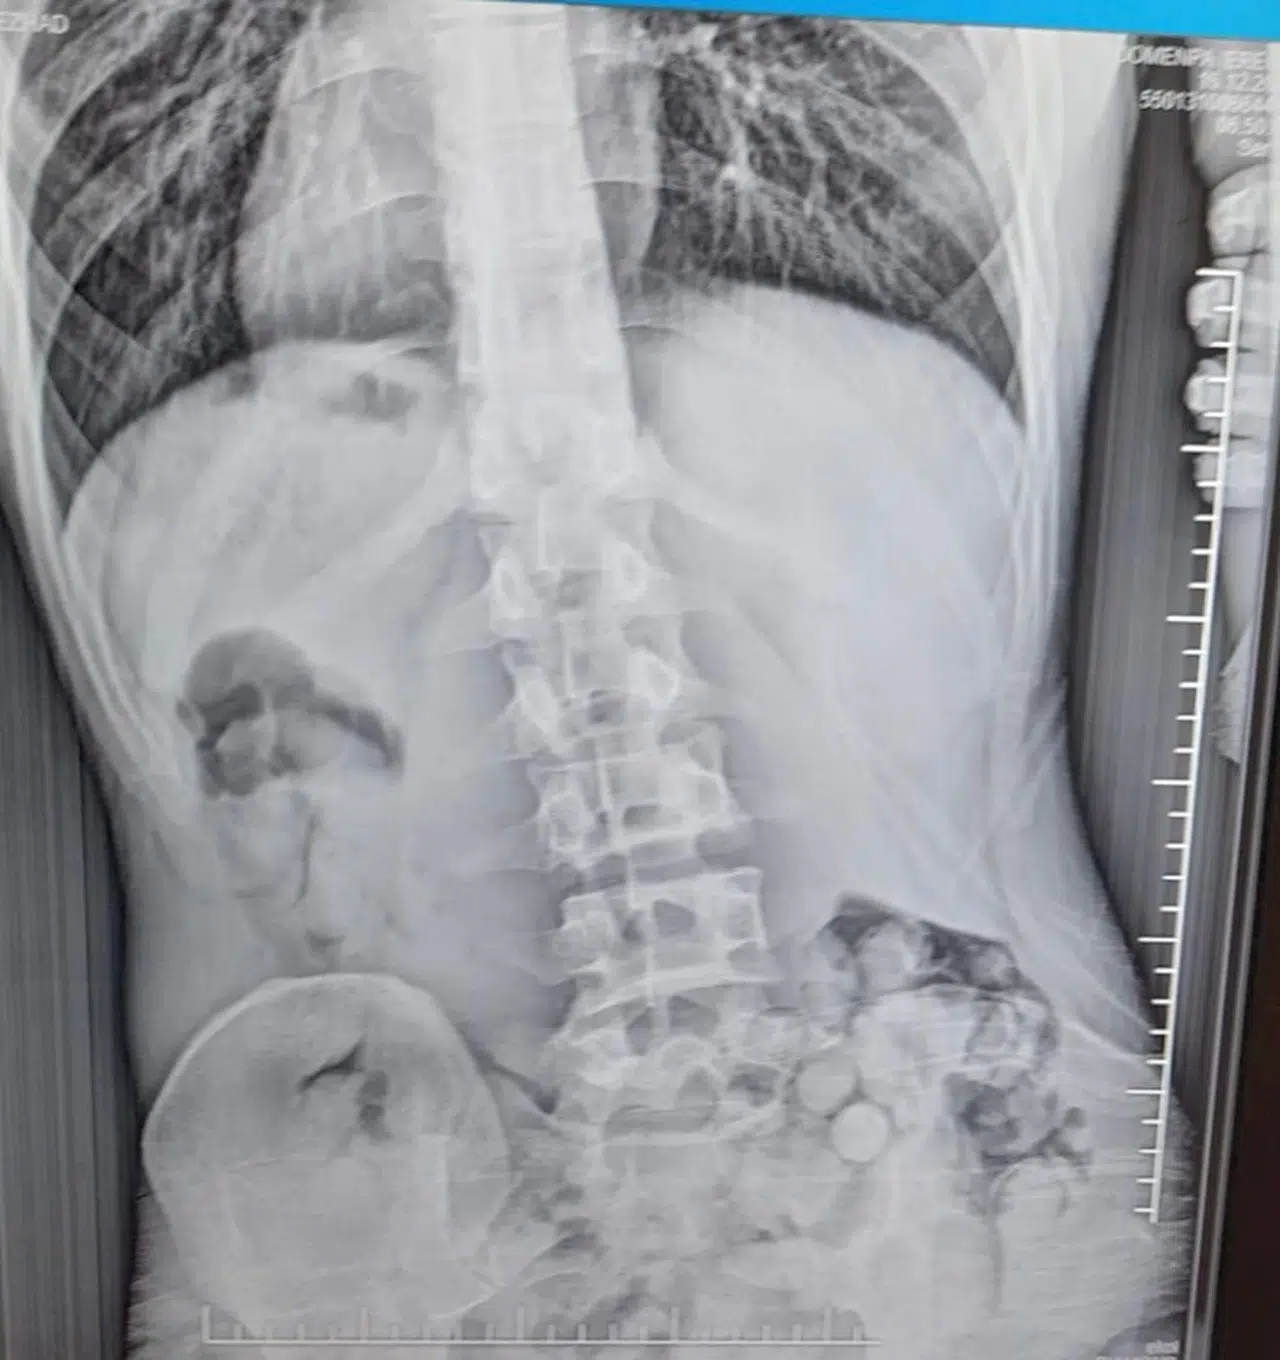

Emre ÖNCEL/SAMSUN, (DHA)- SAMSUN’un Çarşamba ilçesinde midesinde 51 kapsül halinde 309 gram uyuşturucu olduğu tespit edilen R.B. (21), gözaltına alındı.

İl Emniyet Müdürlüğü Narkotik Suçlarla Mücadele Şube Müdürlüğü ekipleri, R.B.’nin, Van’dan Samsun’a yolcu otobüsüyle uyuşturucu getireceği bilgisini aldı. Çarşamba ilçesinde durdurulan yolcu otobüsünde arama yapıldı. Aramalarda, herhangi bir uyuşturucu maddeye rastlanmadı. Polis daha sonra şüpheli hareketler sergileyen R.B.’yi gözaltına aldı. Şüphelinin yapılan iç beden muayenesi sonucunda midesinde 51 kapsül halinde toplam 309 gram metamfetamin tespit edildi. Tıbbi müdahalenin ardından taburcu edilen gözaltındaki şüpheliyle ilgili soruşturma sürüyor. (DHA)

FOTOĞRAFLI